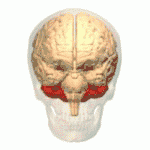

Núcleos profundos

En el interior de la sustancia blanca podemos encontrar 4 pares de núcleos de sustancia gris, que de medial a lateral son: el núcleo del fastigio (o del techo), el globoso, el emboliforme y el dentado. El emboliforme y el globoso está muy relacionados funcionalmente y en conjunto forman el núcleo interpuesto. Los núcleos vestibulares del bulbo raquídeo también funcionan en ciertos aspectos como si fueran núcleos cerebelosos profundos debido a sus conexiones directas con la corteza del lóbulo floculonodular.

El núcleo del fastigio es una masa gruesa con forma de cometa, ubicada casi en la línea media, justo por encima del techo del IV ventrículo del cual está separado por una delgada capa de sustancia blanca. El núcleo globoso es alargado en sentido anteroposterior y se sitúa entre el núcleo del fastigio y el emboliforme. El núcleo emboliforme tiene forma de coma, con la parte gruesa dirigida hacia delante y se sitúa junto al hilio del núcleo dentado.

El núcleo dentado es el de mayor tamaño y se ha calculado que tiene unas 250 000 neuronas. Es de color gris amarillento y tiene forma de bolsa con pliegues abierta hacia delante y hacia la línea media. La abertura se denomina hilio del núcleo dentado y por él salen la mayor parte de las fibras que forman el pedúnculo cerebeloso superior. En el núcleo dentado se distinguen al menos dos tipos de neuronas: las grandes o de proyección y las pequeñas o interneuronas. Pero los circuitos sinápticos de este núcleo no están claramente establecidos. Tanto las neuronas de proyección como las interneuronas tienen prolongaciones no muy numerosas, largas y poco ramificadas, que les dan un aspecto general estrellado.